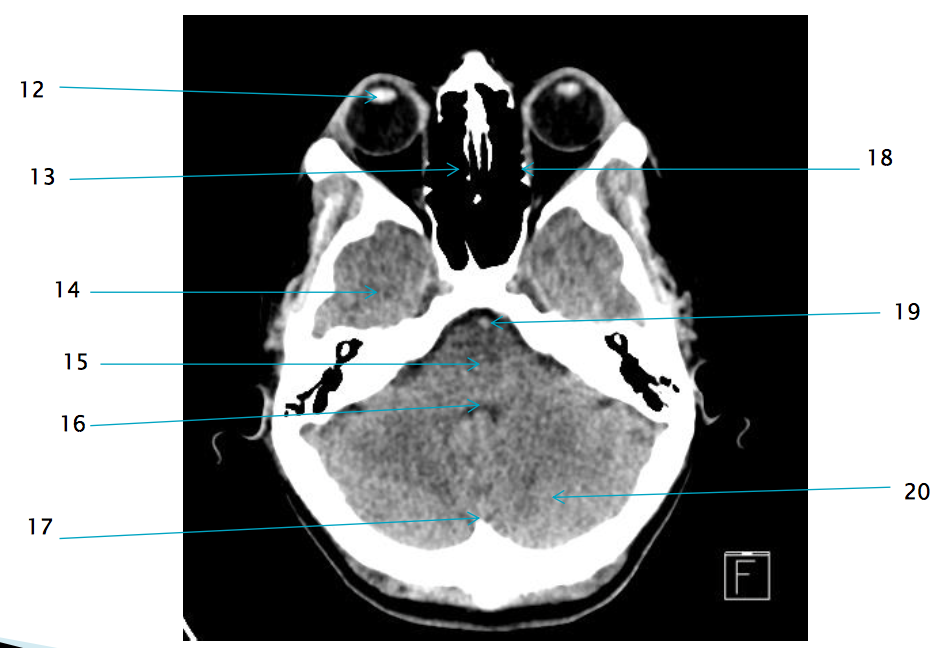

12

lens of R eye

13

ethmoid air cells R

21

R zygomatic bone

17

internal occipital protuberance

19

basilar artery